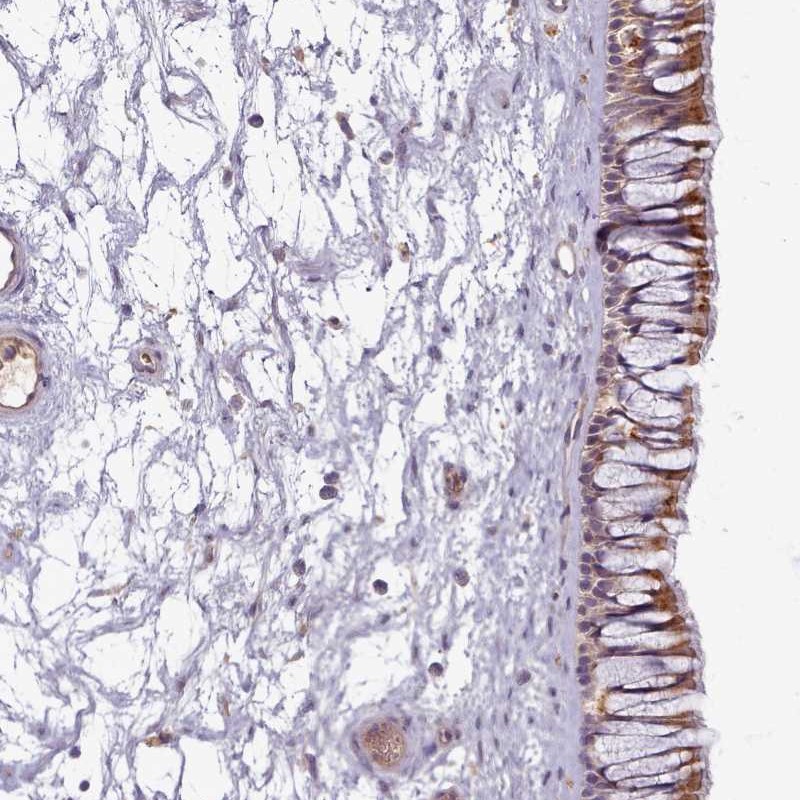

Immunohistochemical staining of human nasopharynx shows moderate cytoplasmic positivity in respiratory epithelial cells.